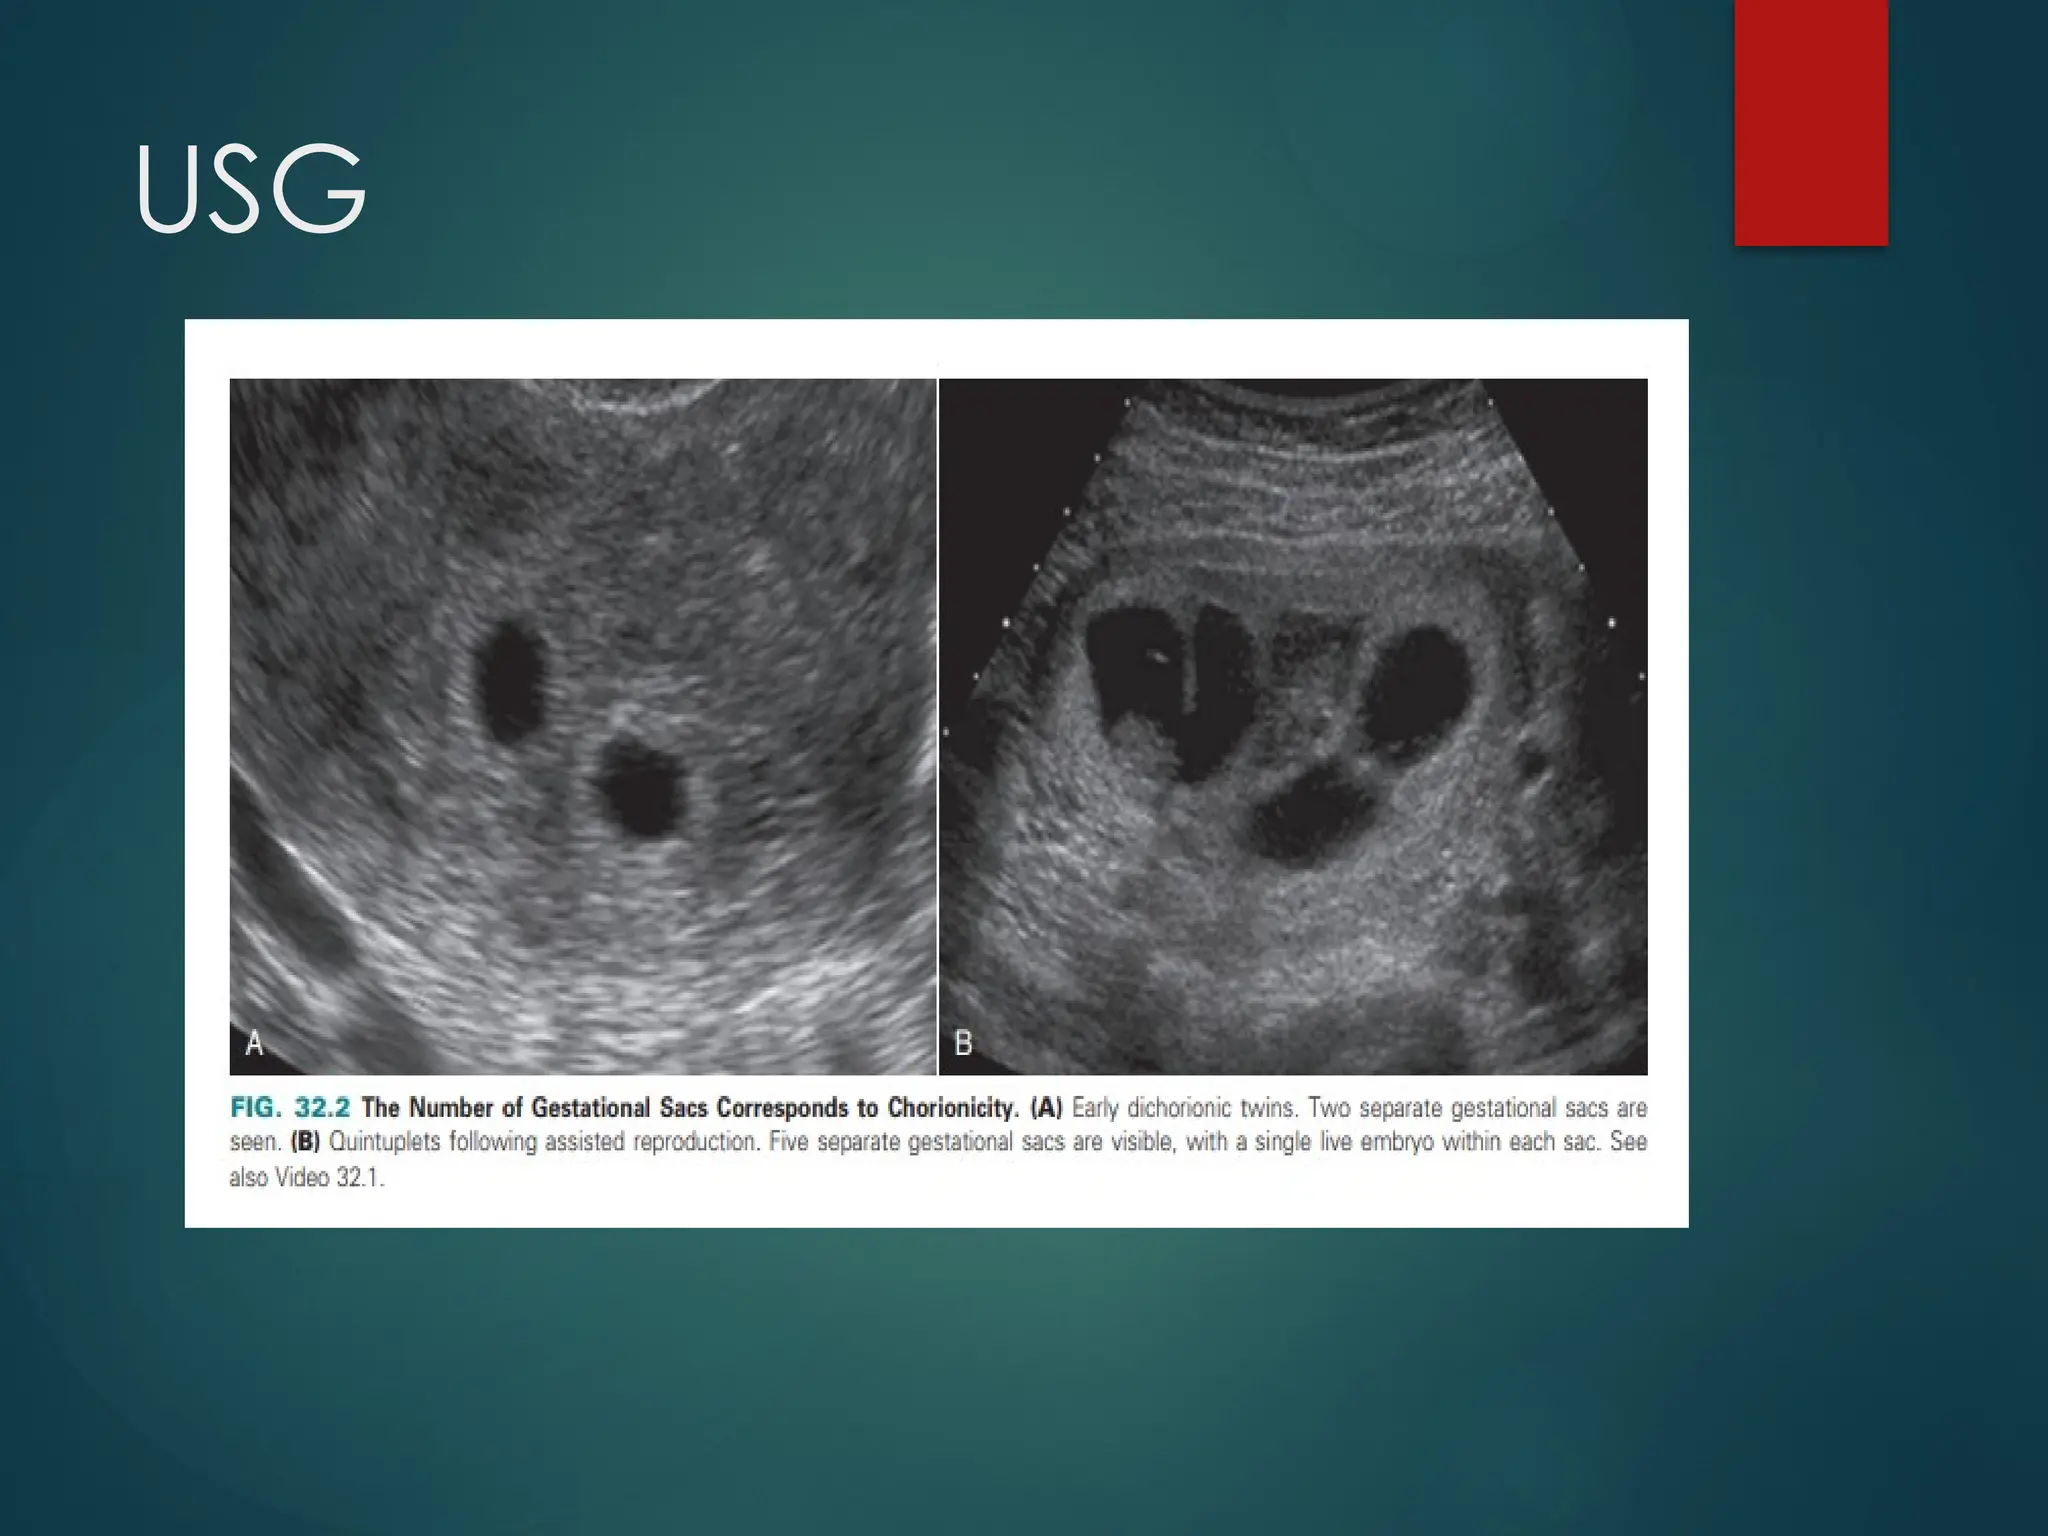

ZYGOSITY/CHORIONICITY

 Twins are either dizygotic or

monozygotic

 Approximately two-thirds are

dizygotic and one-third are

 Dizygotic twins occur when two

separate ova are fertilized by two

separate sperm

 Monozygotic twins occur when a

single ovum is fertilized by a single

sperm

 Dizygotic twins are always

dichorionic diamniotic, meaning

that each twin has its own

placenta (chorion), amnion and

amniotic fluid

There are three possible variations of

chorionicity for monozygotic twins,

who are genetically identical i.e.

-dichorionic

diamniotic

-monochorionic

monoamniotic

USG

Fig: Line diagram of first-trimester pregnancies. Blue, Embryo;

brown, amnion; green, chorion; small black, yolk sac.